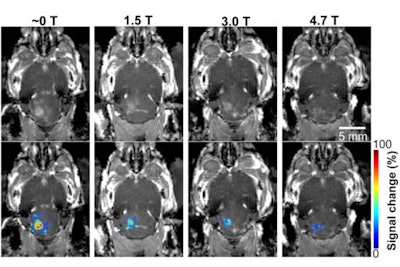

In the study, which included 30 mice, Chen's group discovered that the magnetic field of the MRI scanner reduced the blood-brain barrier's opening volume by 3.3-fold to 11.7-fold, depending on its strength.

"Static magnetic fields dampened microbubble cavitation activity and decreased trans-blood-brain barrier delivery by focused ultrasound combined with microbubble-induced blood-brain barrier opening," the researchers concluded.